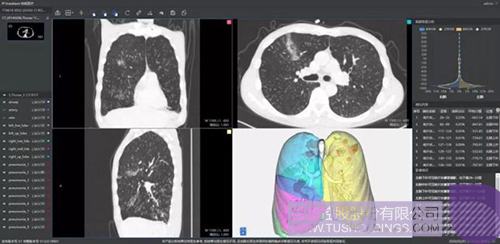

640-3.jpeg

推出的新冠肺炎輔助篩查系統借助AI技術可行之有效地輔助大規模新冠肺炎病例的影像篩查工作。同時基于肺部結構快速智能分割,讓醫生對肺部病變情況一目了然。還可結合臨床征象,自動生成符合最新型冠狀病毒指南的結構化圖文報告,輔助醫生大幅提升診斷效率,同時提高診斷準確性。